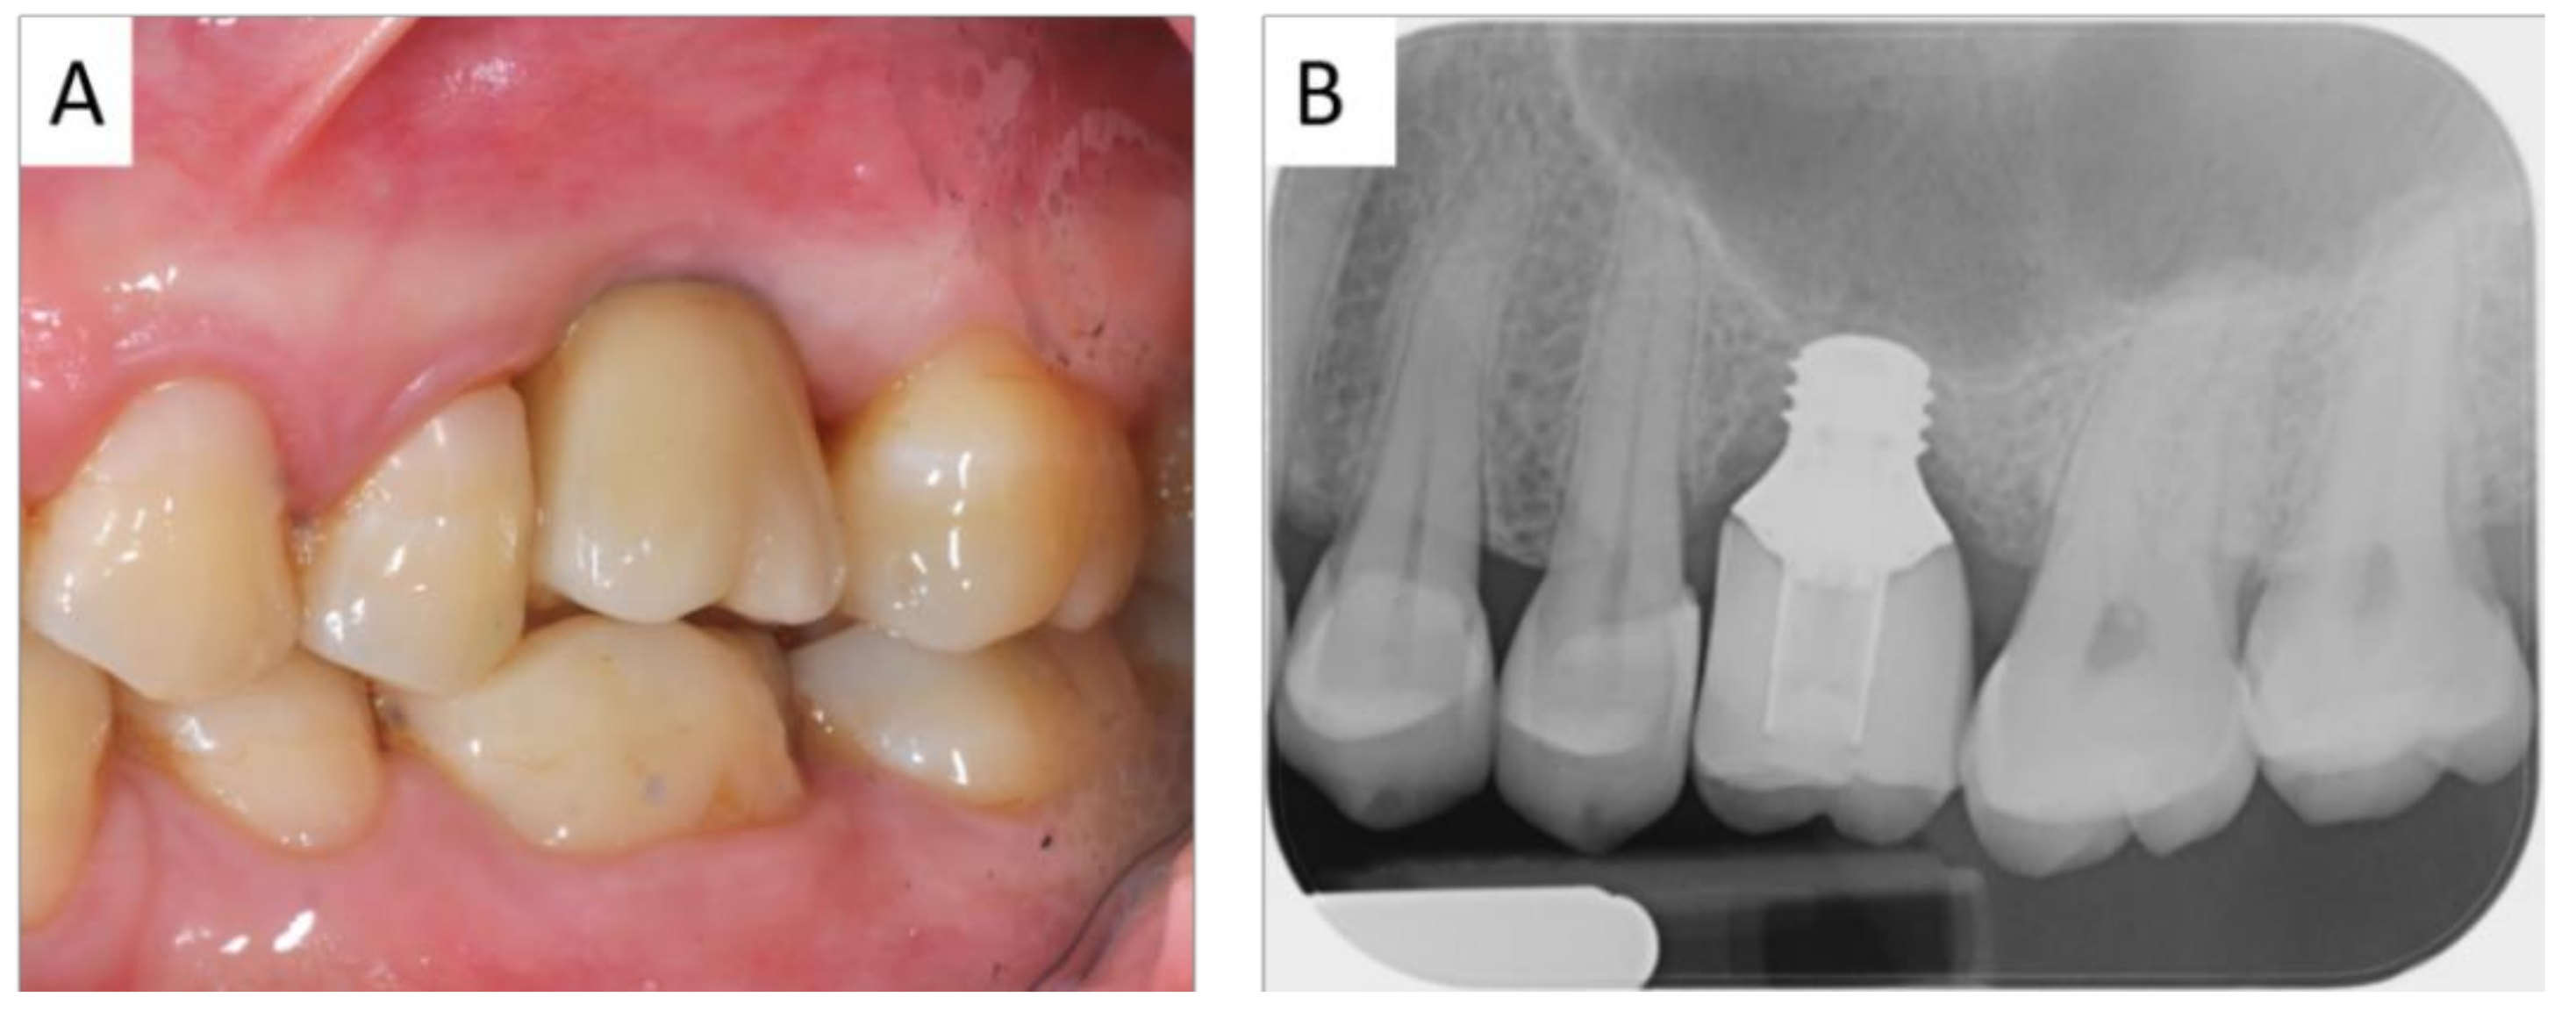

3. Results

4. Discussion